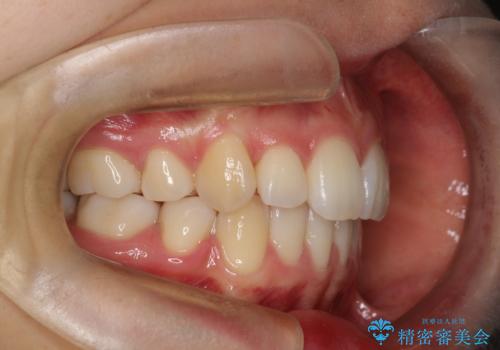

重度のガタガタ ハーフリンガルによる目立たない抜歯矯正

- 八重歯と前歯のガタガタを主訴に来院されました。

目立たない装置をご希望でしたので、上下左右の歯を1本ずつ抜歯してハーフリンガルでの矯正を行いました。

歯並びがコンプレックスで歯を見せて笑うことができなかったとのことですが、歯並びがよくなり、口元を気にせずに笑えるようになったと喜んでいただきました。